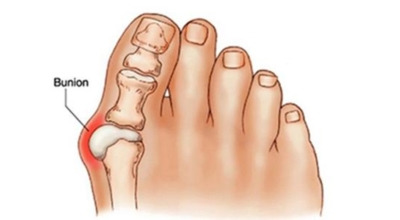

무지외반증이란?

엄지발가락이 두 번째 발가락 쪽으로 과도하게 휘고, 엄지발가락과 연결되는 중족골이 반대로 안쪽으로 기울어지며 발가락이 발등 쪽으로 휘거나 회전(엄지발가락 축을 중심으로 내측으로 회전; 회내)하는 삼차원적인 변형을 말합니다.

육안으로 확연히 엄지발가락의 변형이 보이며, 초기에는 굳은살이 생기고 약간의 통증도 동반됩니다. 엄지발가락의 돌출 부위에 통증이 발생하는데, 이 부위가 신발에 자극을 받아 두꺼워지고 염증이 생겨 통증이 유발됩니다. 발바닥에 굳은살이 생기면 정상적인 보행이 어려워지고, 심한 경우에는 통증 때문에 신발 착용이나 정상적인 보행도 힘들어질 수 있습니다. 증상이 지속적으로 악화되면 엄지발가락이 겹치거나 탈구될 수도 있습니다.